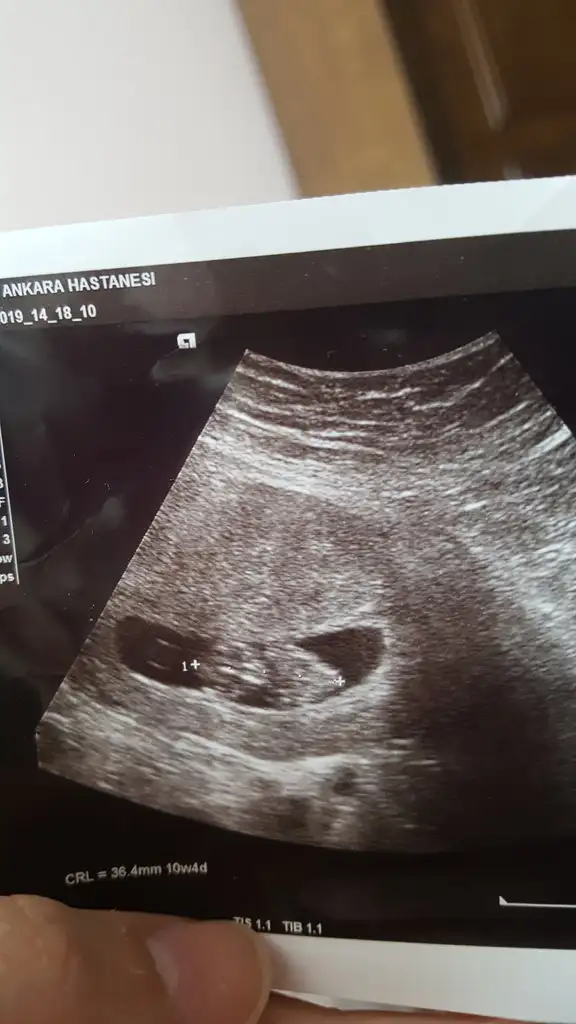

Hoş geldiniz ççok güzel anlatmışsın bebeğiniz hayırlı olsun inş. Geriden gelerek takip yapın dediniz onu nasıl yapacaz yumurtlamanın son saatlerini mi değrlendirelm b.. Yardımcı olursanızKızlar selam, kendi bebeğim in cinsiyeti acaba ne diye bakınırken bu s sayfayı gördüm. Hepinize yazmak istediğim bir hikayem var. İlk bebeğim 24 ikinci 27 yaşında oldu. Allah biliyor ki bende dört yaşında kaybettiğim babamın adını koymak istedim ve hep erkek umdum. Çünkü o içimde derin bir yaraydı. Hiç bir şeye dikkat etmedim bu iki gebelikte düzenli sık ilişkiile oldular hamd olsun. Hemde korunmayı ilk bıraktığım ayda kaldım. Neyse meğer benim oğlum olsa millet kp in ismini k koyacakmış benim de haberim yok sınra Eltim doğum yaptı oğlan kp in adını koyduk bende k kurtuldum. Dört yıl sonra hadi dedim yaş geçmeden kız olsun oğlan olsun üç çocuk olsun sonra da yeter diye niyet ederek hamile kaldım ama kaybettim kürtaj oldum. Kürtaj sonrası kontrol e gidince doktor yakında adet görürsün dedi. Bende adet günüm yakın diye korunmayı bırakıp bir de baktım hamile kalmışım. Sınra gittim kese 11 mm dediler. Sekiz gün sınra tekrar gittim kese hiç büyümemiş yine 11 mm.bebek te oluşmamış gel kürtaj yapalım dediler. Eve geldim birde hastayım iki gün sınra kanama başladı. Dedim eşime hadi acile gidelim bebek düştü ise ilaç alalım. Birde gittik bebek canlanmış kalbi atıyor. Dört aylık olana kadar kanama yaşadım. Hemde ne kanama doğum da görmedim o kadar kan. Hele bir gün akıyor musluk gibi . Tabii biz her kanama bir sürü de parça sonrası bebek gitti diye koşuyoruz dr diyor ki bebek iyi onun etrafında kan yok büyümüş şu kadar olmuş.şaşkın şaşkın eve dönüyoruz. Öyle de tedirginiz nasıl cinsiyet filan aklımıza gelmiyor.12 haftalık ti yine bir kanama sonrası k kontrol e koştuk dr dedi erkek bu bebek. Eşimle bende tık yok. Noldu dedi dr ötekiler de mı erkek ti. Yok dedik onlar kızdı. Sağlık li olsun da o kadar takmışız ki öyle zorlanıyoruz. Neyse doğdu oğlumuz babamın adını koyacağım ya dr muayene de demesin mı kalbi delik olabilir. Bende babamı kalpten kaybettim. Hiç koyalım bile demedim korkumdan...Neyse biz adını başka koyduk olay da yanlış teşhis çıktı çok şükür sağlıkla büyüttük. Ben hep yeter diye düşündüm ama altı yıl sınra eşim başladı istemeye. Ben yeni evliyken bile herkes derdiçocukken benim iki kızım iki oğlum olacak dermis eşim. Neyse oğlan da benim de kardeşim olsun ablamlar hep birlikte benim niye erkek kardeşim yok oynamaya diye. Neyse başka bir sürü sebep te bir araya gelince hadi tamam dedim. Ben akıllı oğlan olsun diye tüm şartları denkledim. Takvimler yumurtlama herşey çok oturdu hatta öyle denk getirdim ki mesela şubat ayında hamile kalacağım ama yaş işte otuz mu otuzbir mı şeyleri var ya çin takviminde dört yıl boyunca şubatta erkek olan yere getirdim. Sınra hamile de kaldım aynı oğlandaki gibi ama daha az kanama da oluyor 13 haftalık gittim kontrol e belki cinsiyetini de öğrenirim diye. Bir baktık bebeği kaybetmişiz. Kürtajla aldılar ramazan ayında orucum. Orucu bile bozmadan girdim kürtaj a nasıl üzgünüm madem dedim bozulacak orucum kaybettiğim bebeğim sahitim olsun. Eve geldim herkes iki gözü iki çeşme zaten zor ikna oldum ya bu kesin doğurmaz bir daha diye. Oğlun deseniz hüngür hüngür. Kv filan hepsi. Baktım eşim çok kötü.Dedim neyin var çok istemiştim dedi. Tamam dedim bir ay daha denerim Rabbim verirse ne ala.kız erkek fark edermi dedim. O nasıl söz dedi keske kız olsaydı da yaşasaydı. İyi o zaman çin takviminde sonraki ay kız a geliyor dedim. Erkek verecekse Rabbim yine verir kız verecekse de kız verir bu sefer hayırlısı olsun dedik. Nur topu gibi kızımız oldu dünya tatlısı. Hep şunu düşündüm Allah bizden bir şeyhi aldı ama muhakkak daha hayırlısını verdi dedim. Hayatımızın en zor iki yılımı geçirdik bebeğimiz bize güç kuvvet oldu. Eşime duyurmadan sürekli içimden iyiki istemiş diye dualar ettim. Şükür oğlan da var kızda dirt yeter dedim. Hep seviyesiz seviyesiz soranlar oldu daha doğuracak mısın diye sanki ard arda doğurdum da millet bakıyor. Hiç büyük konuşmak istemedim başıma gelir diye. Ben düşünmem ama Allah verirse benim için diğerlerinden daha değerli olur dedim. Ben istemişim Allah dört bebek vermiş hemde hep ilk ayda kalmışım. Bu kadar lütuf vermişken Rabbim al bunu da ben veriyorum derse diyecek hicbir sözüm olmaz o bebek benim için ondan gelen bir armağan olur dedim. Demesine de hayatımızın o en zor iki yıllık sürecinin bittiği ay hala da düzenimiz belirsiz iken eşim şehir dışına çıkmıştı bir t yedi sekiz gün sınra gelince bir kaçak yaşadık. Dedim sabah ilk işim ertesi gün hapı almak. Gittim aldım içtim tam adetime 14 gün var hiç riske atmıyorum güya, çok sıkıntımiz var ya düşünmüyorum da zaten. Neyse adet günüm geçti bir gün dedim haptan. Yuksek hormon sonuçta. Gecikmesi normal.iki geçti hadi dedim normal üçüncü gün de gelmeyince baktım ateşim var gibi yanıyorum ateş ölçtüm baya sıcak. Koştum bir test aldım yapıyım negatif çıksın da rahat rahat beklerim adeti diyorum bir yandan da. Testi yaptım ama hani silik çizgi filan iyice bakiyim diyorum bir de baktım kocaman koyuca iki çizgi. Beynimden vurulmuşa döndüm. Kimseye demeden belki test bozuktur diye ertesi gün bir daha yaptım daha koyu bir çizgi gördüm. Bugün 12 haftam bitiyor. Bat günümden beri kanamam oluyor. Arada çok geliyor bebek düştü diye namazi bile bırakıyorum gidiyorum büyümüş yaşıyor diye öğrenip geri geliyorum. Kızlarda çok bulantı yaşardım bunda yaşamıyorum oğlumda da yaşamadım . Rüyamda hep tersini görürüm bunda da kız gördüm bir iki. Ama hamile kalmadan önce çok sıkıntı çekerken başka sorunlar yüzünden rüyamda karnıma bakıldı ultrasonla dedim ki o üç çizgi mı demek ki kızım olur olsun dört kızım olsun dedim. Onunda tabirini sıkıntımızdan kurtulmak diye yordum bebek düşünmüyorum ya. Ertesi ay hamile kaldım. kız erkek hiçbir şey hissetmiyorum. Biliyorum çok ta uzattım ama bu beşinci gebelik e korunmaya çalıştığım halde hamile kalınca şunu gördüm. Bazı arkadaşlar ilişki sonrası ertesi gün hapını hemen içmiş ama hamile kalmış. Benim bir arkadaşım doğum kontrol hapını düzenli içerken hamile kalmış. Başka bir arkadaş spiral le kalmış aldırmış tekrar kalmış spiral le onu doğurmuş doğum da tüpleri bağlatmış. Tüpler bağlı iken hamile kalmış. Sonra bütün bunları da duyunca rahatladım iyice gerçekten de bu güç sadece onun elinde. Ne isterse o oluyor. Ama yaşadığım onca hamilelikte doğumda şunu da fark ettim ki kız spermler uzun erkek spermler kısa yaşıyor. Yumurtlamanın olduğu günü tespit etseniz bile saati bilmiyorsunuz. Eğer boşalma sonrası olursa yumurtlama aynı gün içerisinde bile olsa kızlar çoktan varmış oluyor oraya. Yumurtlama ya göre değil de geriden gelerek denemenizi tavsiye ederim yani saati bile hesaplayarak adetten önce 14. Gün o ay tutmaz sa bir saat daha erken. Tutmazsa iki saat. Döllenmeye hazır bir yumurta olursa ve o anda birleşme olursa işte o zaman ihtimal çok oluyor. Gerçi en büyük ihtimal bu bile olsa ol deyince olduran Rabbim istemezse yine vermez. Kız içinde sürekli düzenli ilişki iki güne bir diyorum isteyen arkadaşlara da yine onda bile olmazsa olmaz da ihtimal yüksek. Ama hayat işte bazen ihtimaller değil de diğerleri gerçek oluyor tıpkı benim ertesi gün hapı ile hamile kalmam gibi . İnşllah Rabbim önce hiç olmayana sonra da ne isteyen varsa onlara hayırlı evlatlar versin istediklerinden. Bende sizden bebeğimi rahat bir şekilde büyütmek için dua bekliyorum inşallah. Çok uzun yazdığım için de özür dilerim bir baktım her şeyi yazmışım hayırlı geceler